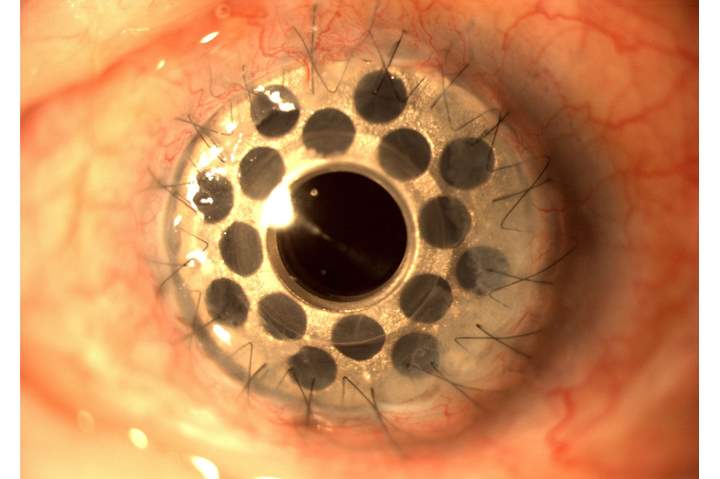

جامعة عين شمس : زراعة أول قرنية صناعية بمصر